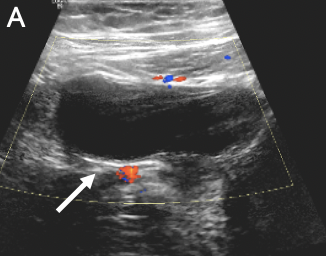

A pelvic ultrasonography scan showed a dilated, blind-ended, fluid-filled tubular structure in the right lower abdomen, which raised suspicion for appendicitis (Figure 1). A pediatric surgeon was consulted, and a computed tomography scan was performed, results of which showed a heterogenous complex lesion within the lower abdominal mesentery. Magnetic resonance imaging (MRI) of the abdomen and pelvis revealed a hydrosalpinx with thick peripheral enhancement, raising suspicion for superimposed infection and inflammation, as well as an arcuate uterus (Figure 2).

Figure 1. Transverse (A) and sagittal (B) views of the ultrasonography scans of the pelvis demonstrated a thick-walled hypoechoic, nonvascular, tubular structure containing internal debris in the left lower abdomen. It is separate from the bowel and bladder, suggestive of pyosalpinx (arrows).